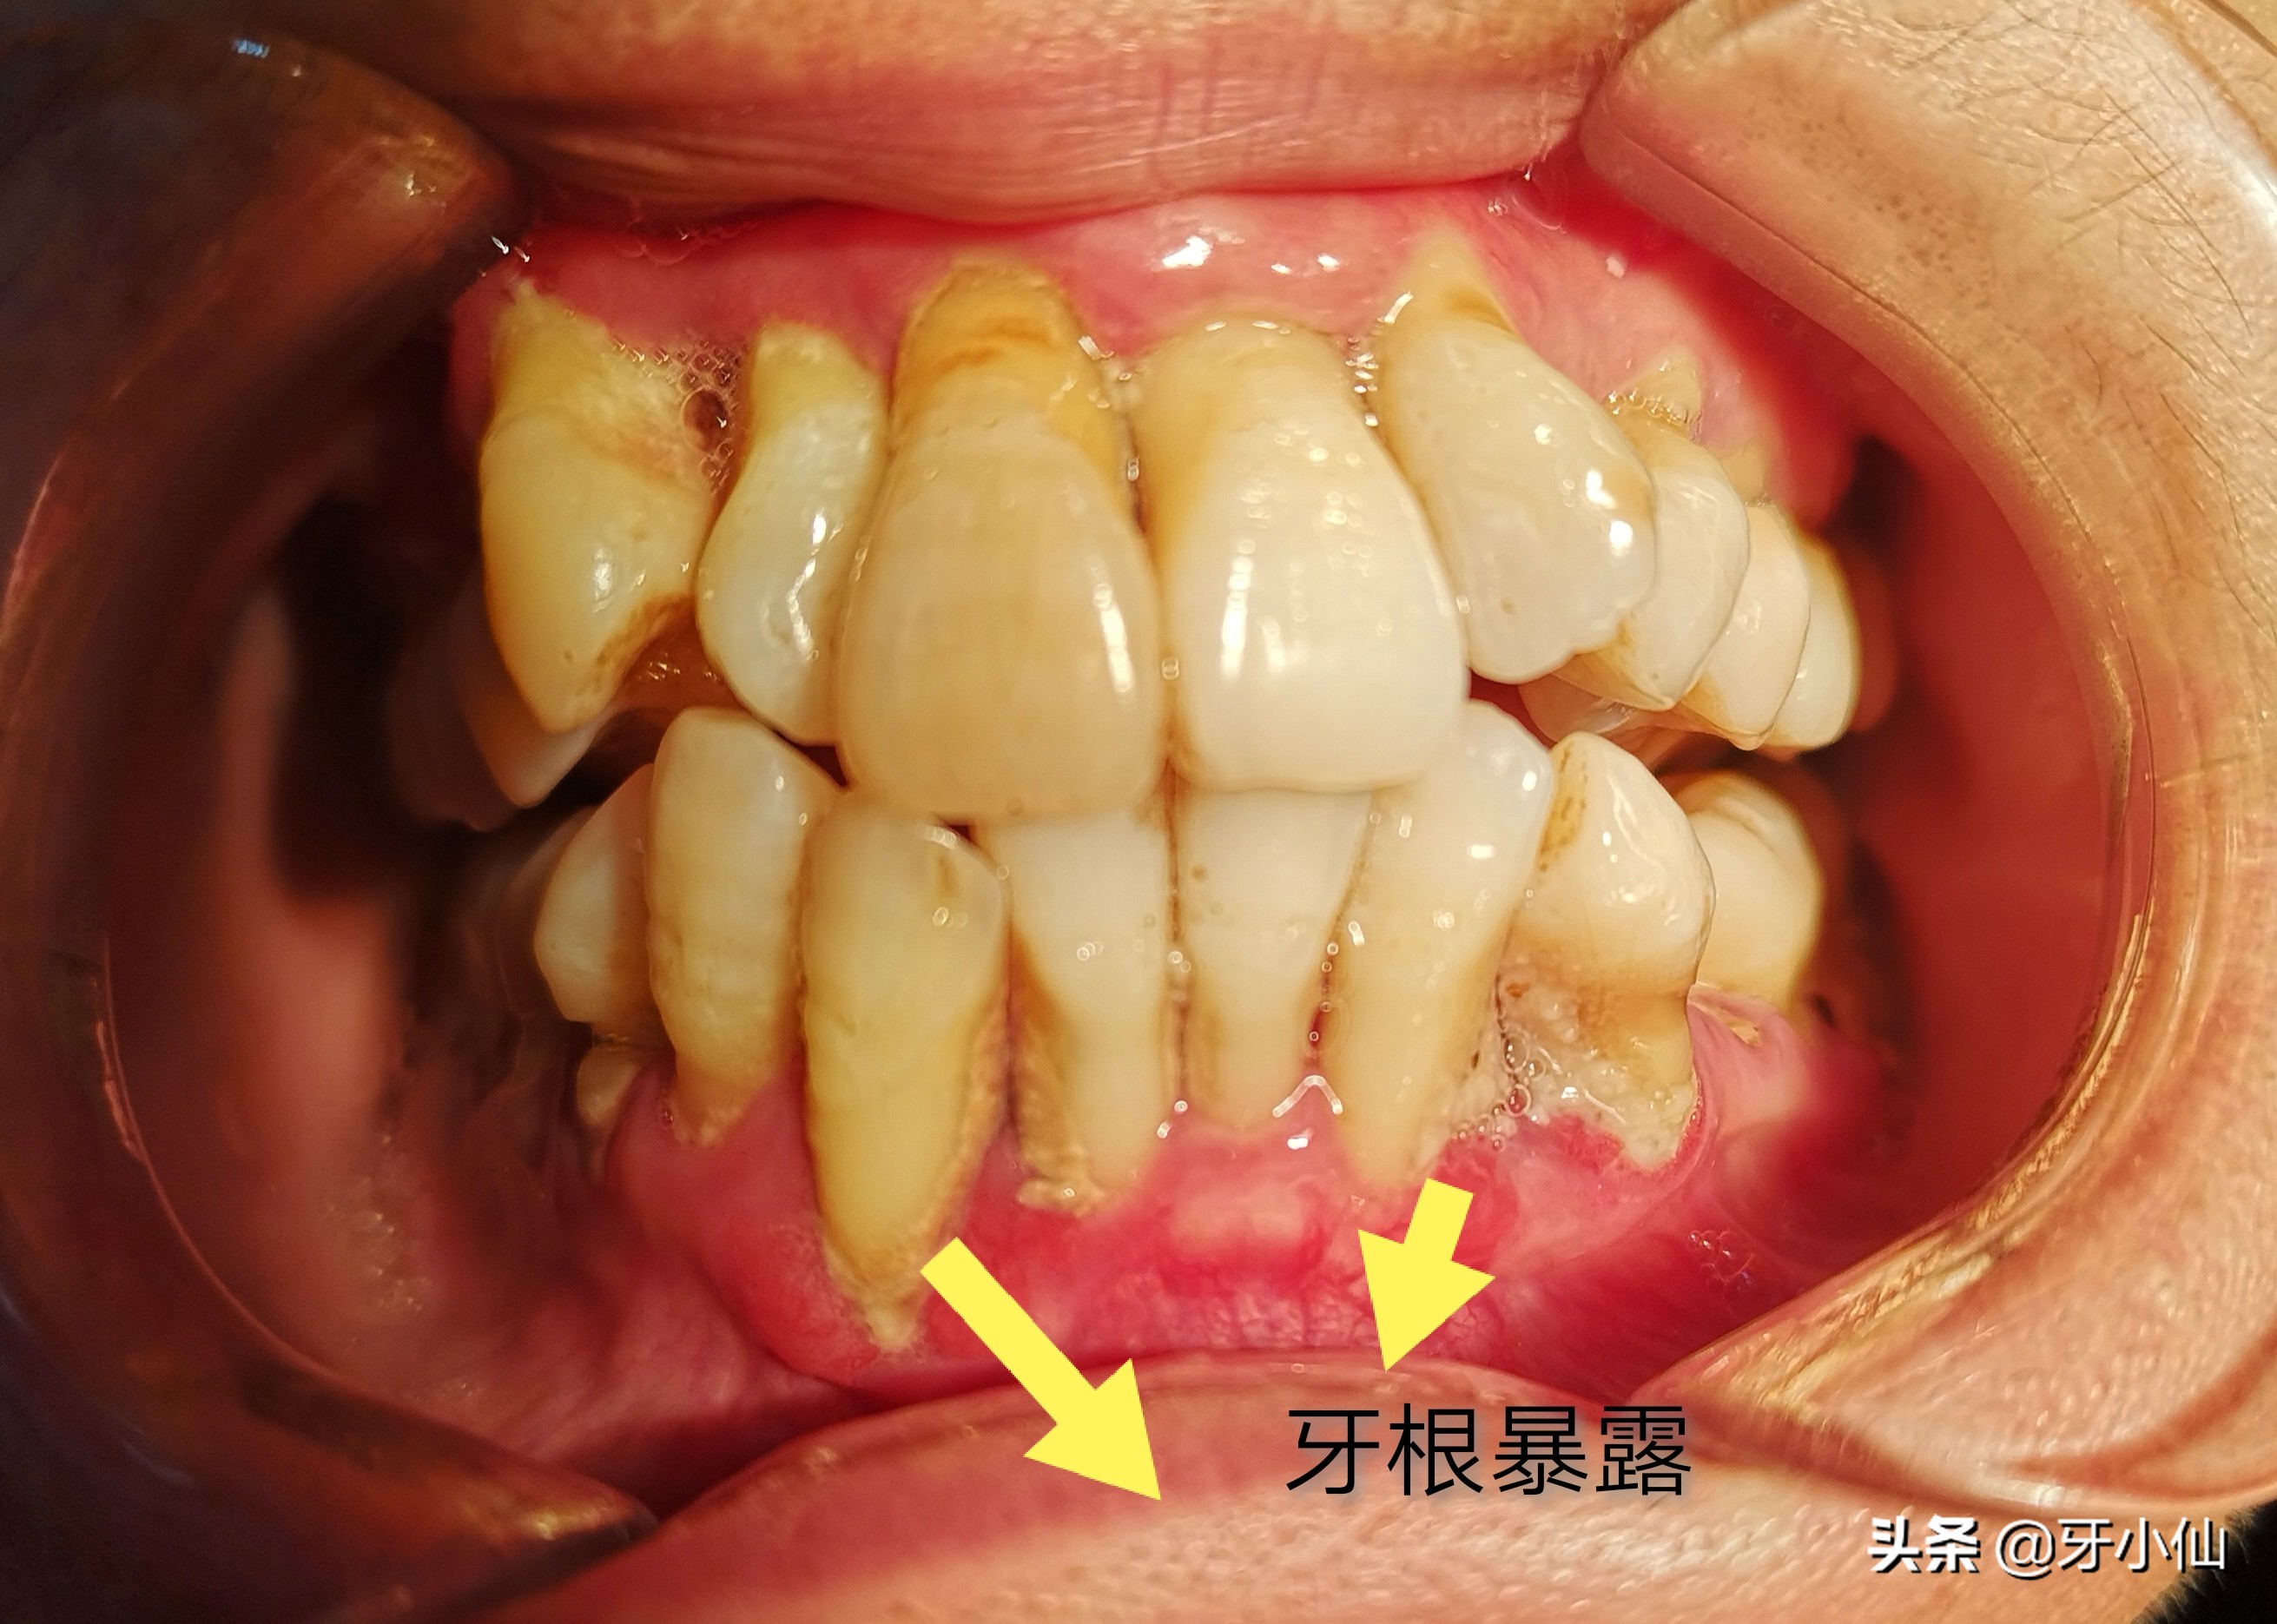

如上图所示,当包裹在牙本质外面的牙釉质缺损、破坏后,牙本质暴露出来。牙齿就会特别敏感。

诊断为:牙周病、牙根暴露、牙本质过敏症

治疗:牙周系统治疗。